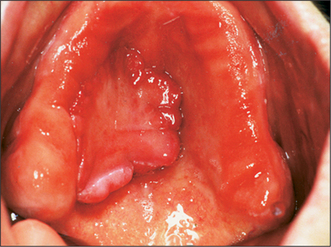

Changes occur in the morphology of the jaws after tooth loss (Fig. 11.1). The jaws are composed of alveolar and basal bone. The alveolar bone and periodontium support the teeth, but neither have a physiological function once the teeth are lost, and are therefore resorbed. Alveolar bone changes shape significantly with tooth loss, in both the horizontal and vertical planes, but the overall pattern of resorption is largely predictable. In the maxilla and in the anterior aspect of the mandible bone loss occurs typically in both the horizontal and vertical planes. In the posterior mandible the bone loss is mostly in the vertical plane.

Fig. 11.1 (a) A dentate mandible, illustrating the extent of supporting (alveolar) bone around the teeth. (b) An edentulous mandible, illustrating the extent of resorption of alveolar bone that occurs following loss of the teeth. Note also that the angle between the ascending ramus and body of the mandible is more obtuse than in (a), and the mental foramen is also closer to the crest of the edentulous ridge. The shaded areas in this illustration indicate areas of resorption of mandibular bone with advancing age.